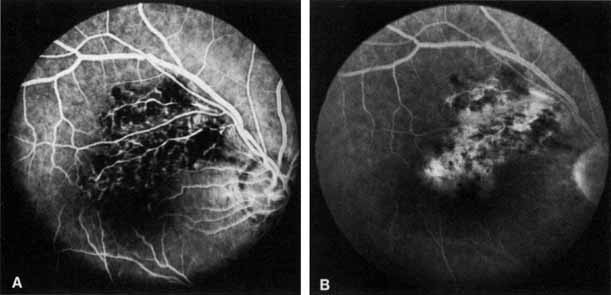

Fig. 1 A. “Blood and thunder” appearance of a central retinal vein occlusion. B. Intravenous fluorescein angiogram shows this occlusion is primarily ischemic or nonperfused. The fact that there is more nonperfusion in the inferior half of the fundus compared with the superior half is unusual.

Coats55 may have been the first to suggest that patients with central retinal vein occlusion fall into two groups: one with a dramatic, “blood and thunder” ophthalmoscopic appearance, loss of vision, and a poor prognosis (see Fig. 1); and the other with mild ophthalmoscopic changes, generally good visual acuity, and a relatively good prognosis (Fig. 2). Other investigators have commented on the difference in severity among central retinal vein occlusions, relying principally on the fluorescein angiogram to assess the severity of occlusion.56–59

Fig. 2 A. Nonischemic central retinal vein occlusion. Note venous engorgement, dot, blot, and flame-shaped hemorrhages, blurring of disc margins, and a hemorrhage overlying the macula. B. Fluorescein angiogram reveals mild venous engorgement and tortuosity with virtually no capillary nonperfusion.

The intravenous fluorescein angiogram pattern of an ischemic central retinal vein occlusion is usually characterized by a delayed filling time of the venous tree of the retina, capillary and venous dilation, and extensive leaking of fluorescein into the retina, particularly in the macular area and in the area adjacent to the larger venous trunks and capillary nonperfusion (see Fig. 3C and 3D; Figs. 4 and 5). Microaneurysms may not be noted at the time of initial occlusion, but are usually manifest shortly thereafter. Late-phase photographs show patchy extravascular areas of fluorescence and staining of the retinal veins. Fluorescence in the macula indicates capillary leakage and edema; this not only may account for much of the initial visual loss in the acute phase, but may also eventually result in permanent structural changes. Intravenous indocyanine green videoangiography may also be helpful in showing the arterial and venous flow alterations in this condition.322

Fig. 4 Fluorescein angiogram after moderately ischemic central retinal vein occlusion. A. Early venous phase. The capillary bed is dilated and engorged. Punctate areas of fluorescence represent microaneurysms or small areas of capillary leakage. B. Midvenous phase. There is considerable delay in venous return and an increase in and coalescence of punctate areas of extravascular fluorescence. C. Late venous phase. Fluorescence staining along the vein margins and scattered areas of capillary nonperfusion (arrow) are present.

Fig. 5 Fluorescein angiogram of acute ischemic retinal vein occlusion. Capillary nonperfusion is essentially 100%.